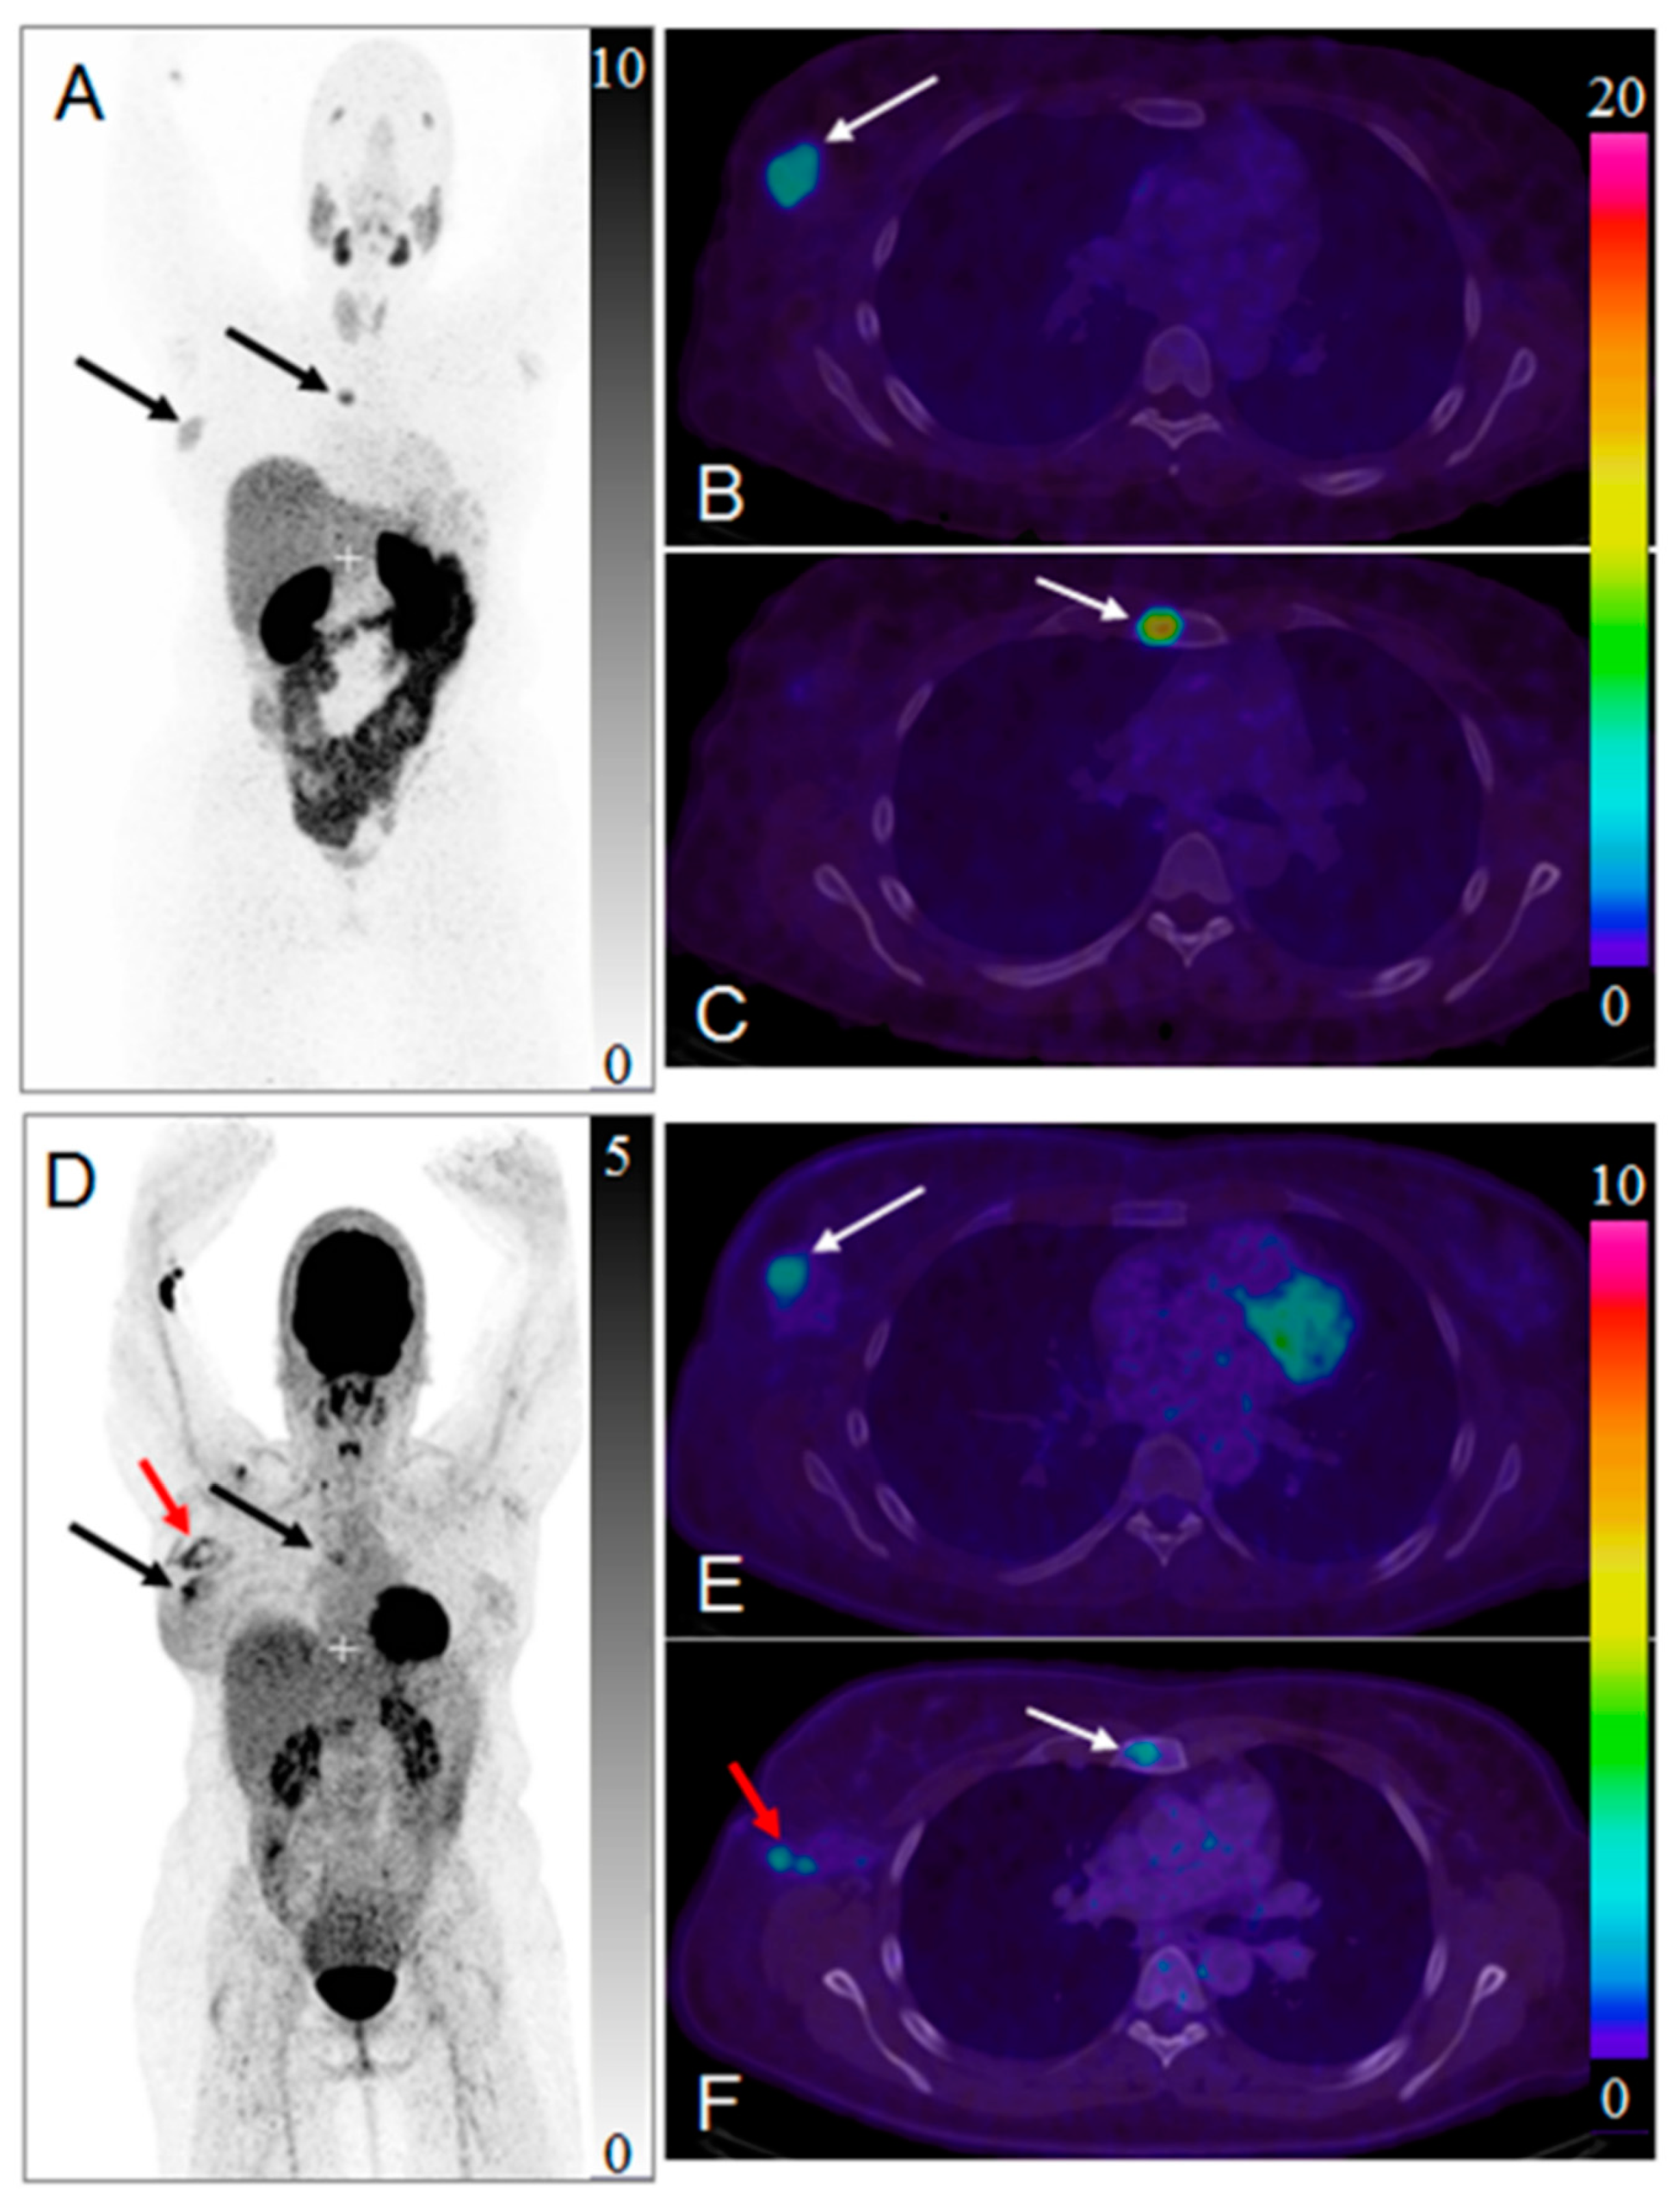

Figure 9.

(A) Pre-therapeutic imaging using [68Ga]Ga-PSMA-11 PET/CT delivering highest resolution; (B) Co-emission of γ-rays by Lu-177 enables imaging during therapy with [177Lu]Lu-PSMA-617; (C) 99mTc-PSMA scintigraphy has minimally less noise than posttherapy scanning and can be used for imaging follow-up in out-patient setting. GM 5 geometric mean; MIP 5 maximum-intensity projections; p.i. 5 after injection. Reproduced from [132].